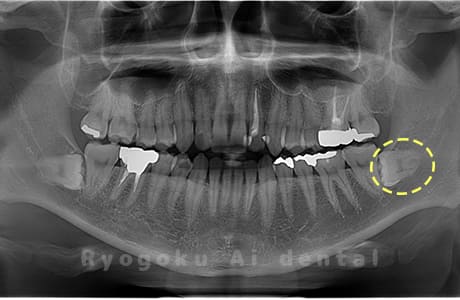

Case09

- 原因

- 下顎左の水平埋伏智歯

- 治療内容

- 下顎左の水平埋伏智歯を抜歯したケースです。

<リスク・副作用>

手術後は痛み、腫れ、痺れなどの副作用が生じる場合があります。